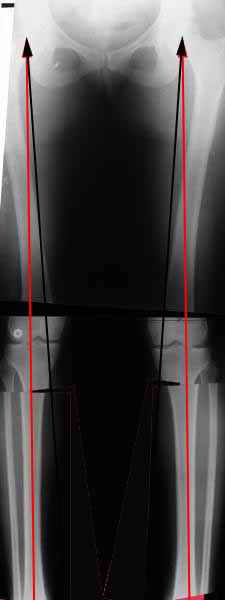

Вот, с учетом и без учета, и на разных уровнях...

Черные - это нынешняя механическая ось. Красные - это планируемая правильная ось.